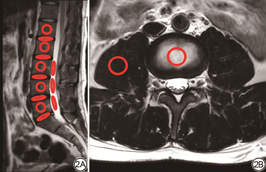

将扫描所得图像传至ISP(Philips, IntelliSpace Portall Version7)工作站,由两名观察者(观察者1为从事MRI工作5年的主管技师,观察者2为从事MRI工作4年的技师)在矢状位T1WI、T2WI椎体最大层面划定感兴趣区(region of interest, ROI),测量L1~L5椎体、间盘信号强度(signal intensity, SI)和噪声强度标准差(standard deviation, SD),ROI大小分别为140~150 mm2、40~50 mm2,并在L3~L5水平划定三个ROI测量脑脊液SI和SD,大小20~30 mm2,取平均值。在轴位T2WI划定ROI测量L1~L5椎体、间盘SI和SD值,ROI大小140~150 mm2,并在L3~L5水平划定ROI测量右侧腰大肌SI和SD,大小40~50 mm2(图2),取平均值。计算信噪比(signal to noise ratio, SNR)和对比噪声比(contrast to noise ratio, CNR)[5]。矢状位T1WI、T2WI:SNR=SI椎体或间盘/SD脑脊液,CNR=(SI椎体或间盘-SI脑脊液)/SD脑脊液;轴位T2WI:SNR=SI椎体或间盘/SD腰大肌,CNR=(SI椎体或间盘-SI脑脊液)/SD腰大肌。